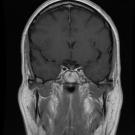

A 26-year-old woman presented to the emergency department (ED) with progressive confusion and recurrent falls. The patient reported having vomiting and diarrhea for 1 week and several falls 1 day before her...

11/30/2024